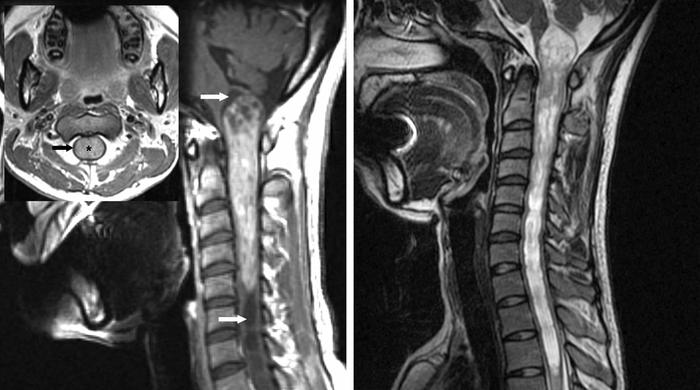

1:所示颈髓室管膜瘤典型影像学表现:不均匀强化,肿瘤上下极脊髓空洞(白色箭头),呈对称性膨胀性生长,正常脊髓被挤压变薄(黑色箭头,左图).注意髓内空洞两端的T2相高信号(右图)